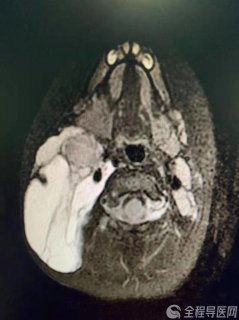

颈部的肿块

张女士带着孩子,来到徐州市儿童医院介入科,李炯主任看到这个孩子的颈部有一个芒果大小的肿块,为孩子检查后确诊是淋巴管瘤,他告诉张女士治疗很简单,不用太担心。